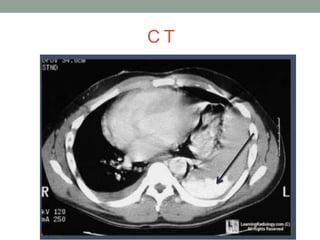

C T

• CT

• INDICATION

• USES- POST OP FOLLOW UP OF IMPROVEMENT